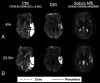

Sodium MR imaging has the potential to complement routine proton MR imaging examinations with the goal of improving diagnosis, disease characterization, and clinical monitoring in neurologic diseases. In the past, the utility and exploration of sodium MR imaging as a valuable clinical tool have been limited due to the extremely low MR signal, but with recent improvements in imaging techniques and hardware, sodium MR imaging is on the verge of becoming clinically realistic for conditions that include brain tumors, ischemic stroke, and epilepsy. In this review, we briefly describe the fundamental physics of sodium MR imaging tailored to the neuroradiologist, focusing on the basics necessary to understand factors that play into making sodium MR imaging feasible for clinical settings and describing current controversies in the field. We will also discuss the current state of the field and the potential future clinical uses of sodium MR imaging in the diagnosis, phenotyping, and therapeutic monitoring in neurologic diseases.